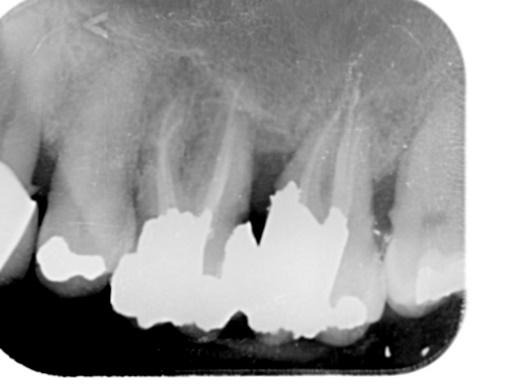

Lower Molar x2 curved roots Primary Root canal treatment and dental crown/rebuild